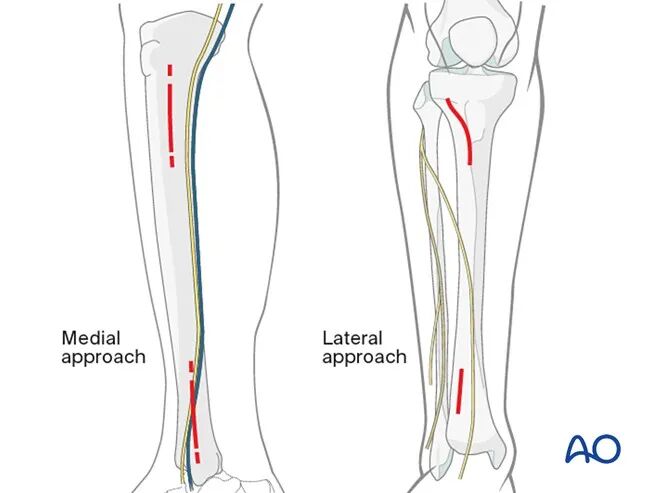

手术入路

●若软组织条件允许,优先选择内侧入路,该入路便于经皮置入螺钉,且软组织干扰较小。

●若内侧软组织条件不佳,则选择外侧入路。

●若闭合复位无法达到满意效果,需及时转为切开复位。